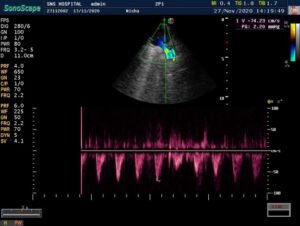

CARDIAC screening of the baby was done – is fourth week of life. Showed –

> Acyanotic congenital heart disease.

VSD – 5mm – muscular non –

restrictive.

ASD – 4mm – L-R shunt

PDA – 2.5mm – L-R shunt. Baby under follow up.